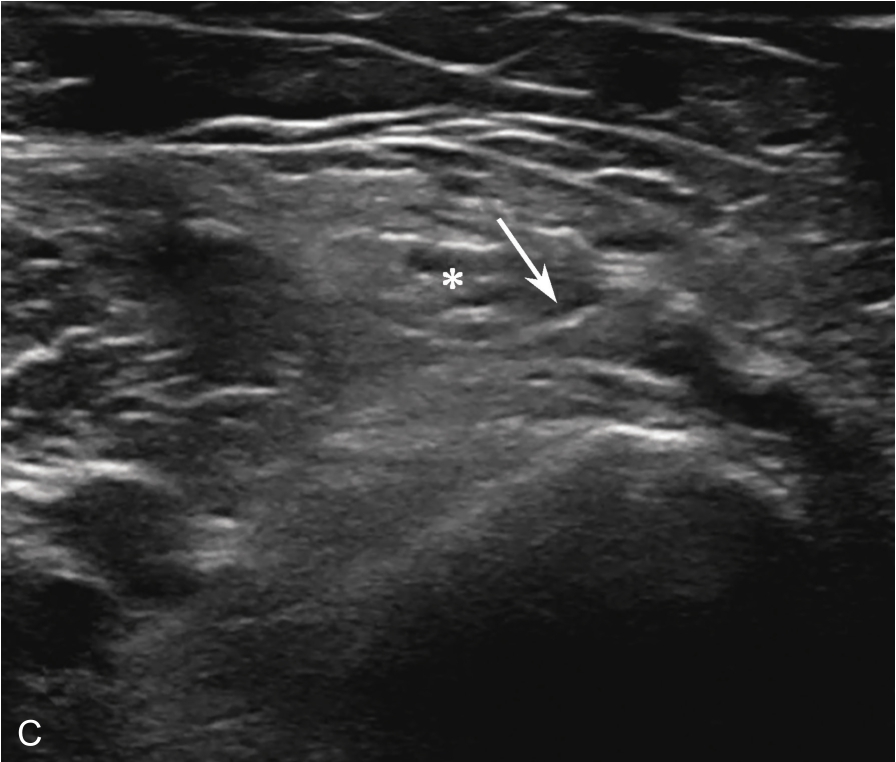

平面内进针法,从内向外或从外向内引导针尖进入滑囊后进行药物注射(图2-1-3、图 2-1-4)。

▲ 图2-1-4 超声引导下肩峰下-三角肌下滑囊注射治疗超声图

箭头:穿刺针;星号:滑囊

2.当针尖进入滑囊后(图2-1-5),可推注少量药物,若推注顺利可观察到滑囊扩张及药物的弥散(图2-1-6),同时也表明针尖准确位于滑囊内,可继续推注混合药物3~5ml。若推注受阻,原因有可能是针尖在滑囊组织内,需重新调整针尖,也可能是滑囊内粘连明显所致,可加大力度,利用液体推注的压力松解粘连,松解后可见粘连带呈线状稍强回声(图2-1-7),也可在粘连远端重新选择部位注入药物,这类患者可能需要多次治疗才能达到较好的疗效。